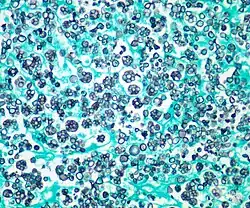

| Histologic stain of a Prototheca zopfii infection in a dog | |

Protothecosis, otherwise known as Algaemia, is a disease found in dogs, cats, cattle, and humans caused by a type of green alga known as Prototheca that lacks chlorophyll and enters the human or animal bloodstream. It and its close relative Helicosporidium are unusual in that they are actually green algae that have become parasites.[1] The two most common species are Prototheca wickerhamii and Prototheca zopfii. Both are known to cause disease in dogs, while most human cases are caused by P. wickerhami.[2] Prototheca is found worldwide in sewage and soil. Infection is rare despite high exposure, and can be related to a defective immune system.[3] In dogs, females and Collies are most commonly affected.[4]

Prototheca has been thought to be a mutant of Chlorella, a type of single-celled green alga. However, while Chlorella contains galactose and galactosamine in the cell wall, Prototheca lacks these. Also, Chlorella obtains its energy through photosynthesis, while Prototheca is saprotrophic, feeding on dead and decaying organic matter. When Prototheca was first isolated from slime flux of trees in 1894, it was thought to be a type of fungus.[6] Its size varies from 2 to 15 micrometres.[7]

Disseminated protothecosis is most commonly seen in dogs. The algae enters the body through the mouth or nose and causes infection in the intestines. From there it can spread to the eye, brain, and kidneys. Symptoms can include diarrhea, weight loss, weakness, inflammation of the eye (uveitis), retinal detachment, ataxia, and seizures.[11]

Dogs with acute blindness and diarrhea that develop exudative retinal detachment should be assessed for protothecosis.[6] Diagnosis is through culture or finding the organism in a biopsy, cerebrospinal fluid, vitreous humour, or urine. Treatment of the disseminated form in dogs is very difficult, although use of antifungal medication has been successful in a few cases.[4] Prognosis for cutaneous protothecosis is guarded and depends on the surgical options. Prognosis for the disseminated form is grave. This may be due to delayed recognition and treatment.[3]